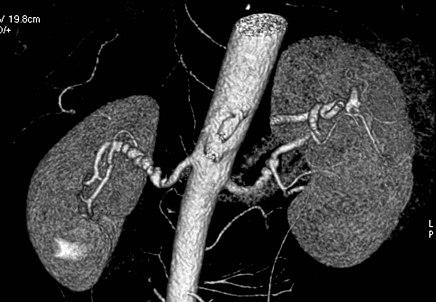

Volume rendered CTA of renal arteries in patient with medial fibromuscular dysplasia.

Visualization of blood flow in the renal arteries (those supplying the kidneys) in patients with high blood pressure and those suspected of having kidney disorders can be performed using CTA. Stenosis (narrowing) of a renal artery is a cause of hypertension (high blood pressure) in some patients and can be corrected. A special computerized method of viewing the images makes renal CT angiography a very accurate examination.[5] CTA is also used in the assessment of native and transplant renal arteries.[2] While CTA is great for imaging of the kidneys, it lacks the ability to perform procedures at the same time. Thus traditional catheter angiography is used in cases of acute renal hemorrhage or acute arterial obstruction.[1]